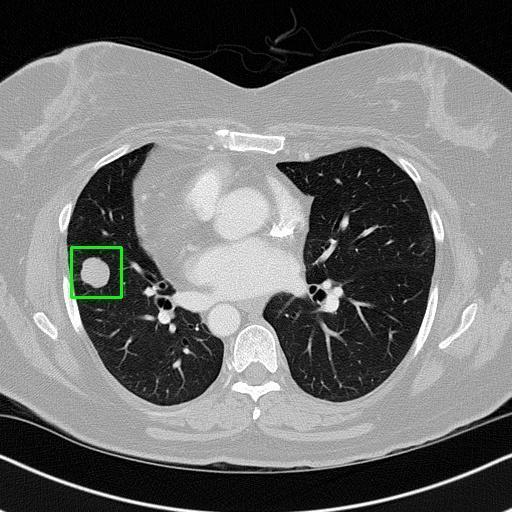

We developed an AI-based system using deep learning models for analyzing lung CT scans to detect and classify pulmonary nodules. We chose the YOLOv11 architecture for its enhanced object detection capability and adapted it specifically for medical imaging, incorporating pixel-level precision and severity classification.

Classification into three severity levels with colored bounding boxes.

Successfully built and deployed an AI model (YOLOv11) capable of detecting lung nodules in CT scans with high accuracy and real-time performance.

Designed a severity classification system that categorizes nodules into null, moderate, and severe using colored bounding boxes, assisting in rapid clinical decision-making.